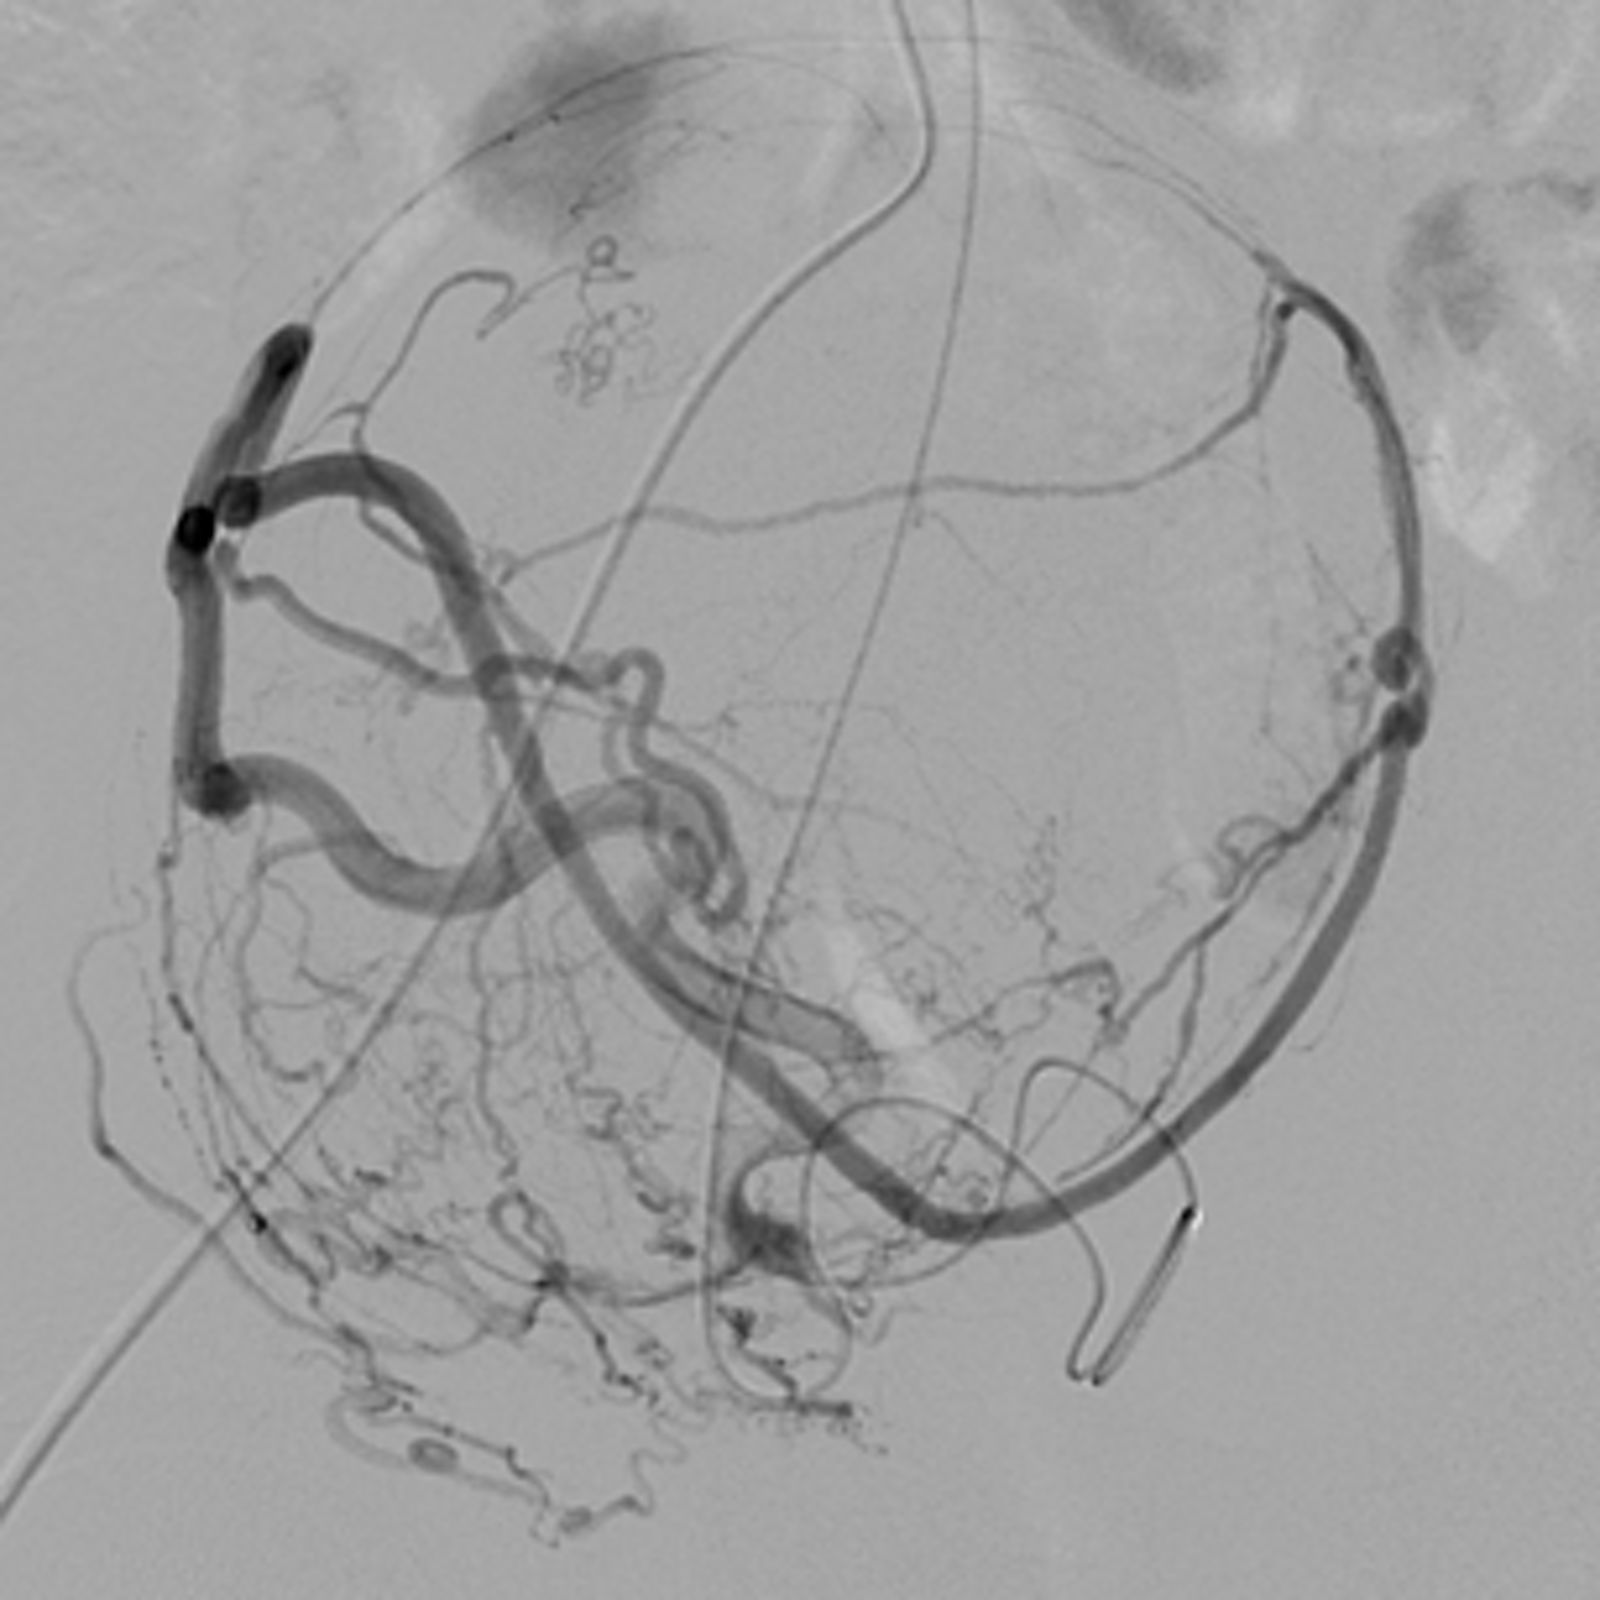

Vergleich der Myom-Durchblutung vor und nach der Embolisation